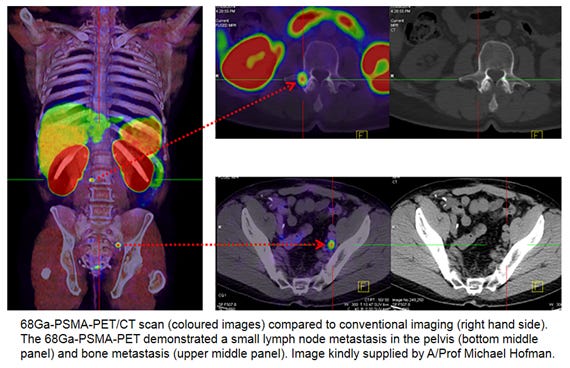

Is PSMA PET/CT More Beneficial than Bone Scintigraphy in Detecting

Guiding management of therapy in prostate cancer: time to switch

PSMA-PET is rapidly changing the standard of care for prostate

Guiding management of therapy in prostate cancer: time to switch